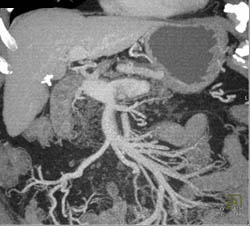

Hemangioma